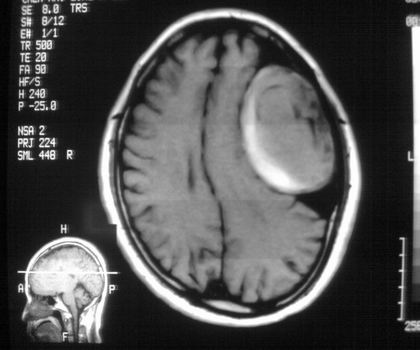

以下是引用影像孺子牛在2008-4-29 21:20:00的发言:[br]首先病变定位在脑外,根据ct密度及mri信号特征考虑慢性硬膜下血肿不连续环形钙化。

以下是引用周战梅在2008-4-29 23:12:00的发言:[br]脑外病变,蛛网膜下腔增宽,囊壁点状、环形钙化,增强扫描呈不均匀环状强化,考虑为囊性脑膜瘤可能性大,慢性脓肿、血肿机化、胆脂瘤不能除外。